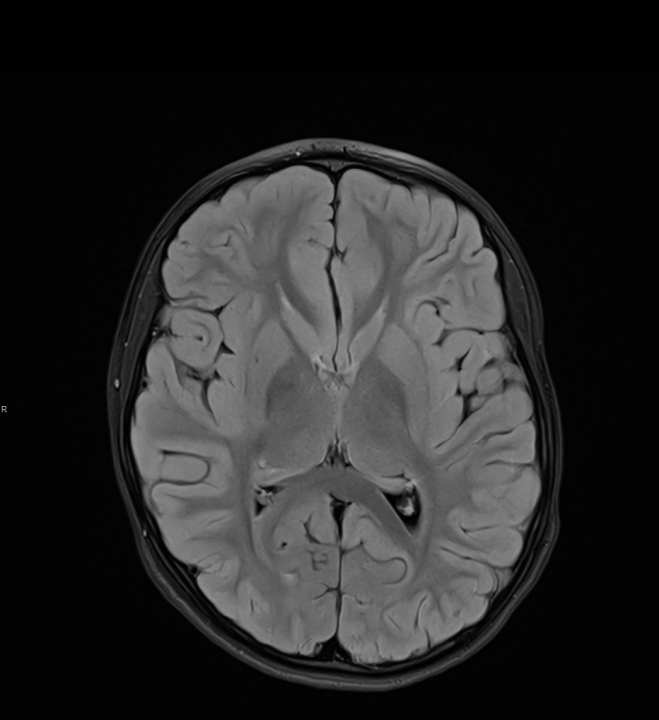

Tijekom Tjedna mozga Poliklinika Affidea Vita daje 20 posto popusta na magnetsku rezonancu!

Povodom obilježavanja Tjedna mozga od 11.